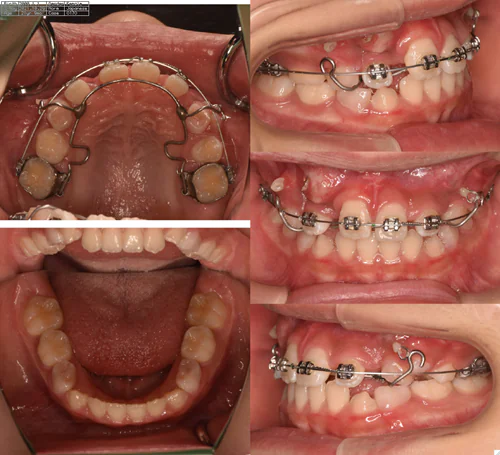

case.8(中村様)

治療前 治療中 治療後

治療開始の年齢 12歳1ヶ月

治療名

開窓牽引

治療内容

埋伏歯の開窓牽引配列

費用 770,000円

治療期間

1年3ヶ月